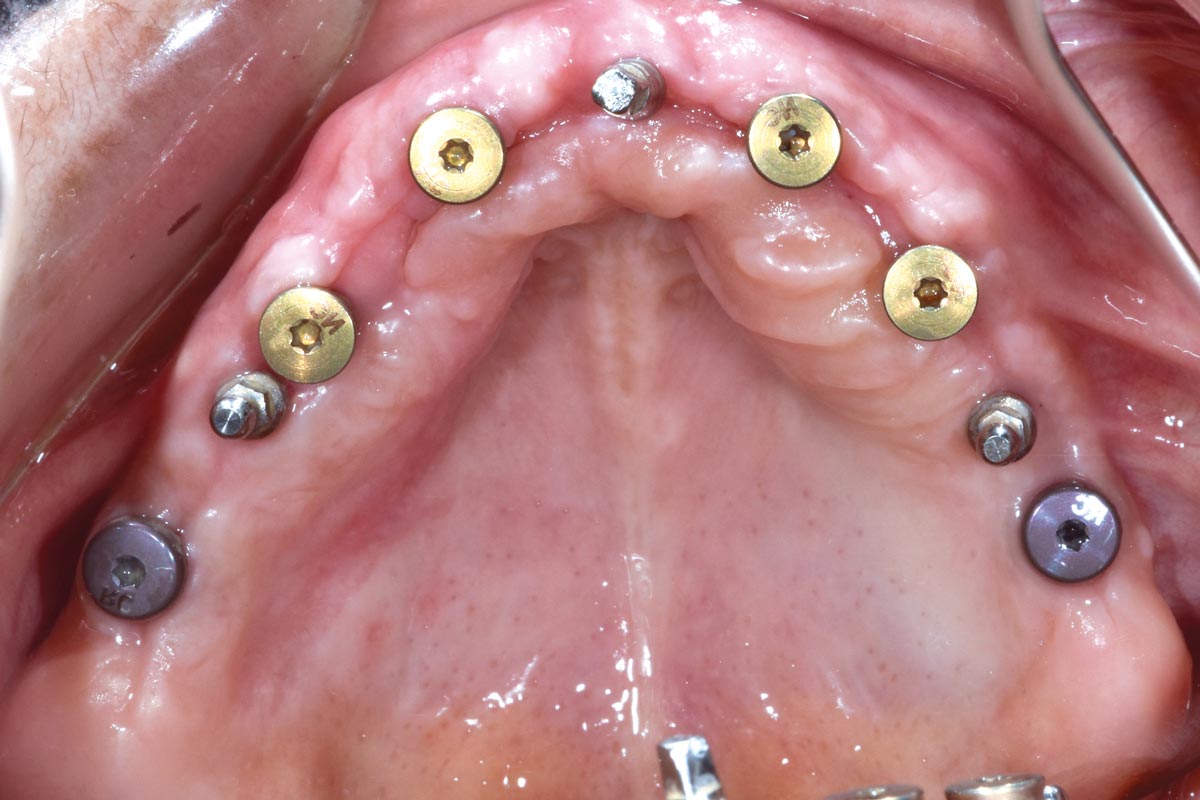

Full arch GBR using cerabone®, maxgraft® and Jason® membrane with simultaneous implantation of 6 Straumann® implants - Dres. A. Signorio and G. Molina